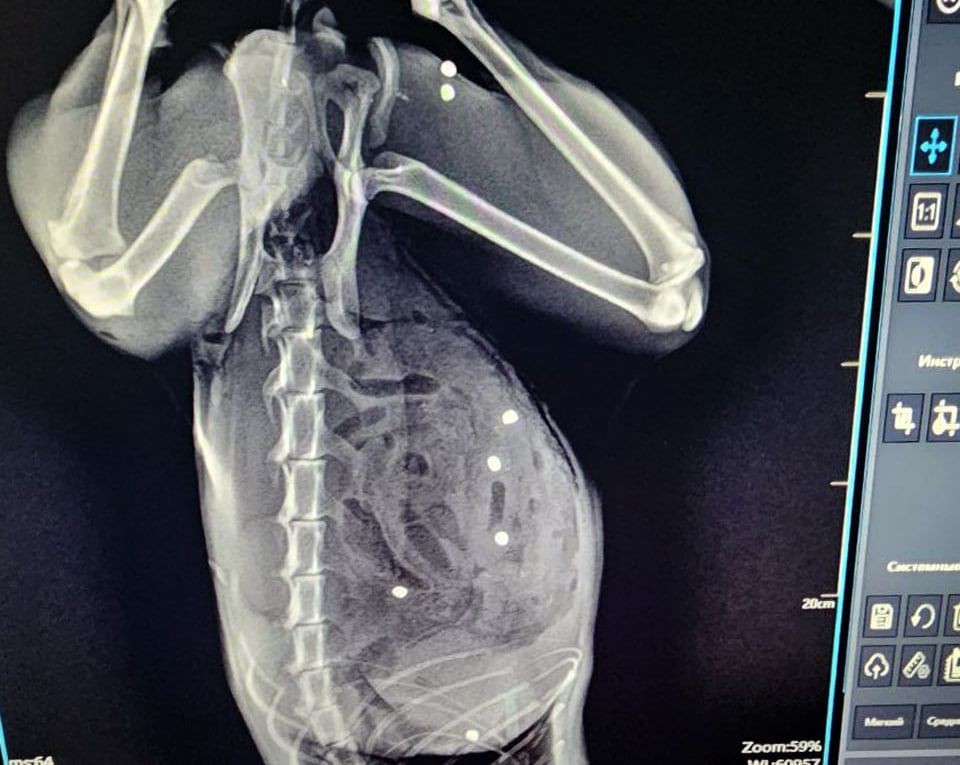

У животного в 24 местах был пробит кишечник и в двух местах — селезенка. Также пули попали в грудную клетку и мышцы бедра. Операция длилась более трех часов. Пациента, которого считали почти безнадежным, спасли, сказано в сообщении.

«Под конец операции и кот, и я выглядели одинаково… Не скрою, горжусь собой на 100%, но ещё больше котом! Несмотря нa все усилия живодёров, котик жив!» — рассказал хирург Евгений Цыбин.